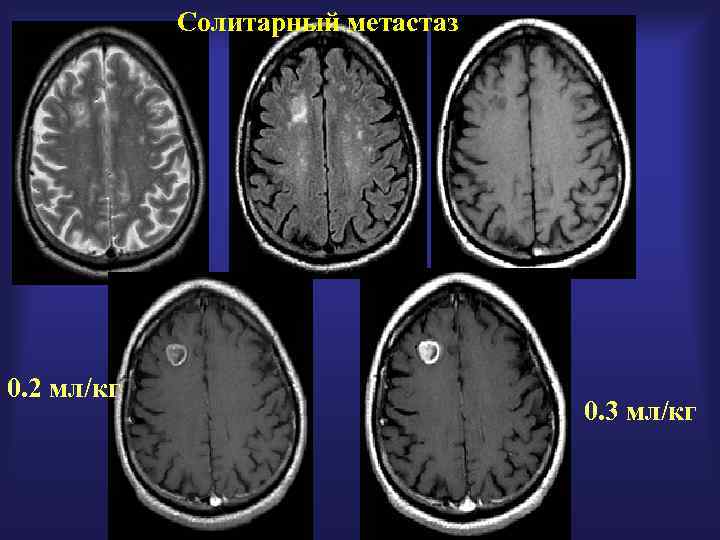

Солитарный метастаз 0. 2 мл/кг 0. 3 мл/кг